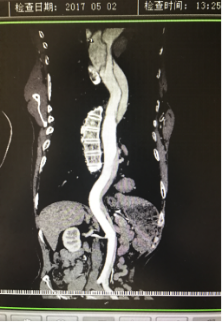

5月2號劉大伯照常早起干活,突然胸部劇烈疼痛,難以忍受,全身大汗,同時伴有右上肢發(fā)涼,他心想這次心絞痛比之前嚴重的多啊,趕緊叫上孩子到吉林國文醫(yī)院心血管內科住院,患者長期高血壓病史,血壓一直控制不理想,大夫給他做了檢查,測左上肢血壓:82/45mmHg,右上肢血壓測不出,心率52次/分,右側肱動脈、尺動脈、橈動脈搏動消失,左側股動脈搏動較右側弱?!霸懔耍p側血壓差別這么大,是不是主動脈夾層了?”,接診大夫趕緊找來李主任,李主任反復詢問患者病情,表情突然凝重起來,患者胸痛這么明顯,血壓低的厲害,主動脈夾層的可能性很大。二話不說,李主任立即聯(lián)系影像科的醫(yī)生準備做主動脈CTA,移動患者做檢查的過程大夫們非常小心,嚴密監(jiān)測患者血壓變化情況。兩個小時后結果出來了,主動脈夾層從升主動脈一直撕裂到左側髂總動脈!?。?/p>

從開始學醫(yī)到現(xiàn)在已經(jīng)快9年了,主動脈夾層患者也見過一些,但像劉大伯這種危險類型的還是第一次見到,心里真的為他捏把汗,撕裂的主動脈隨時都有可能破裂,生命隨時可能終止,要知道主動脈夾層的死亡率非常的高,約50%的患者發(fā)病后48小時死亡,約90%的患者發(fā)病1個月內死亡。